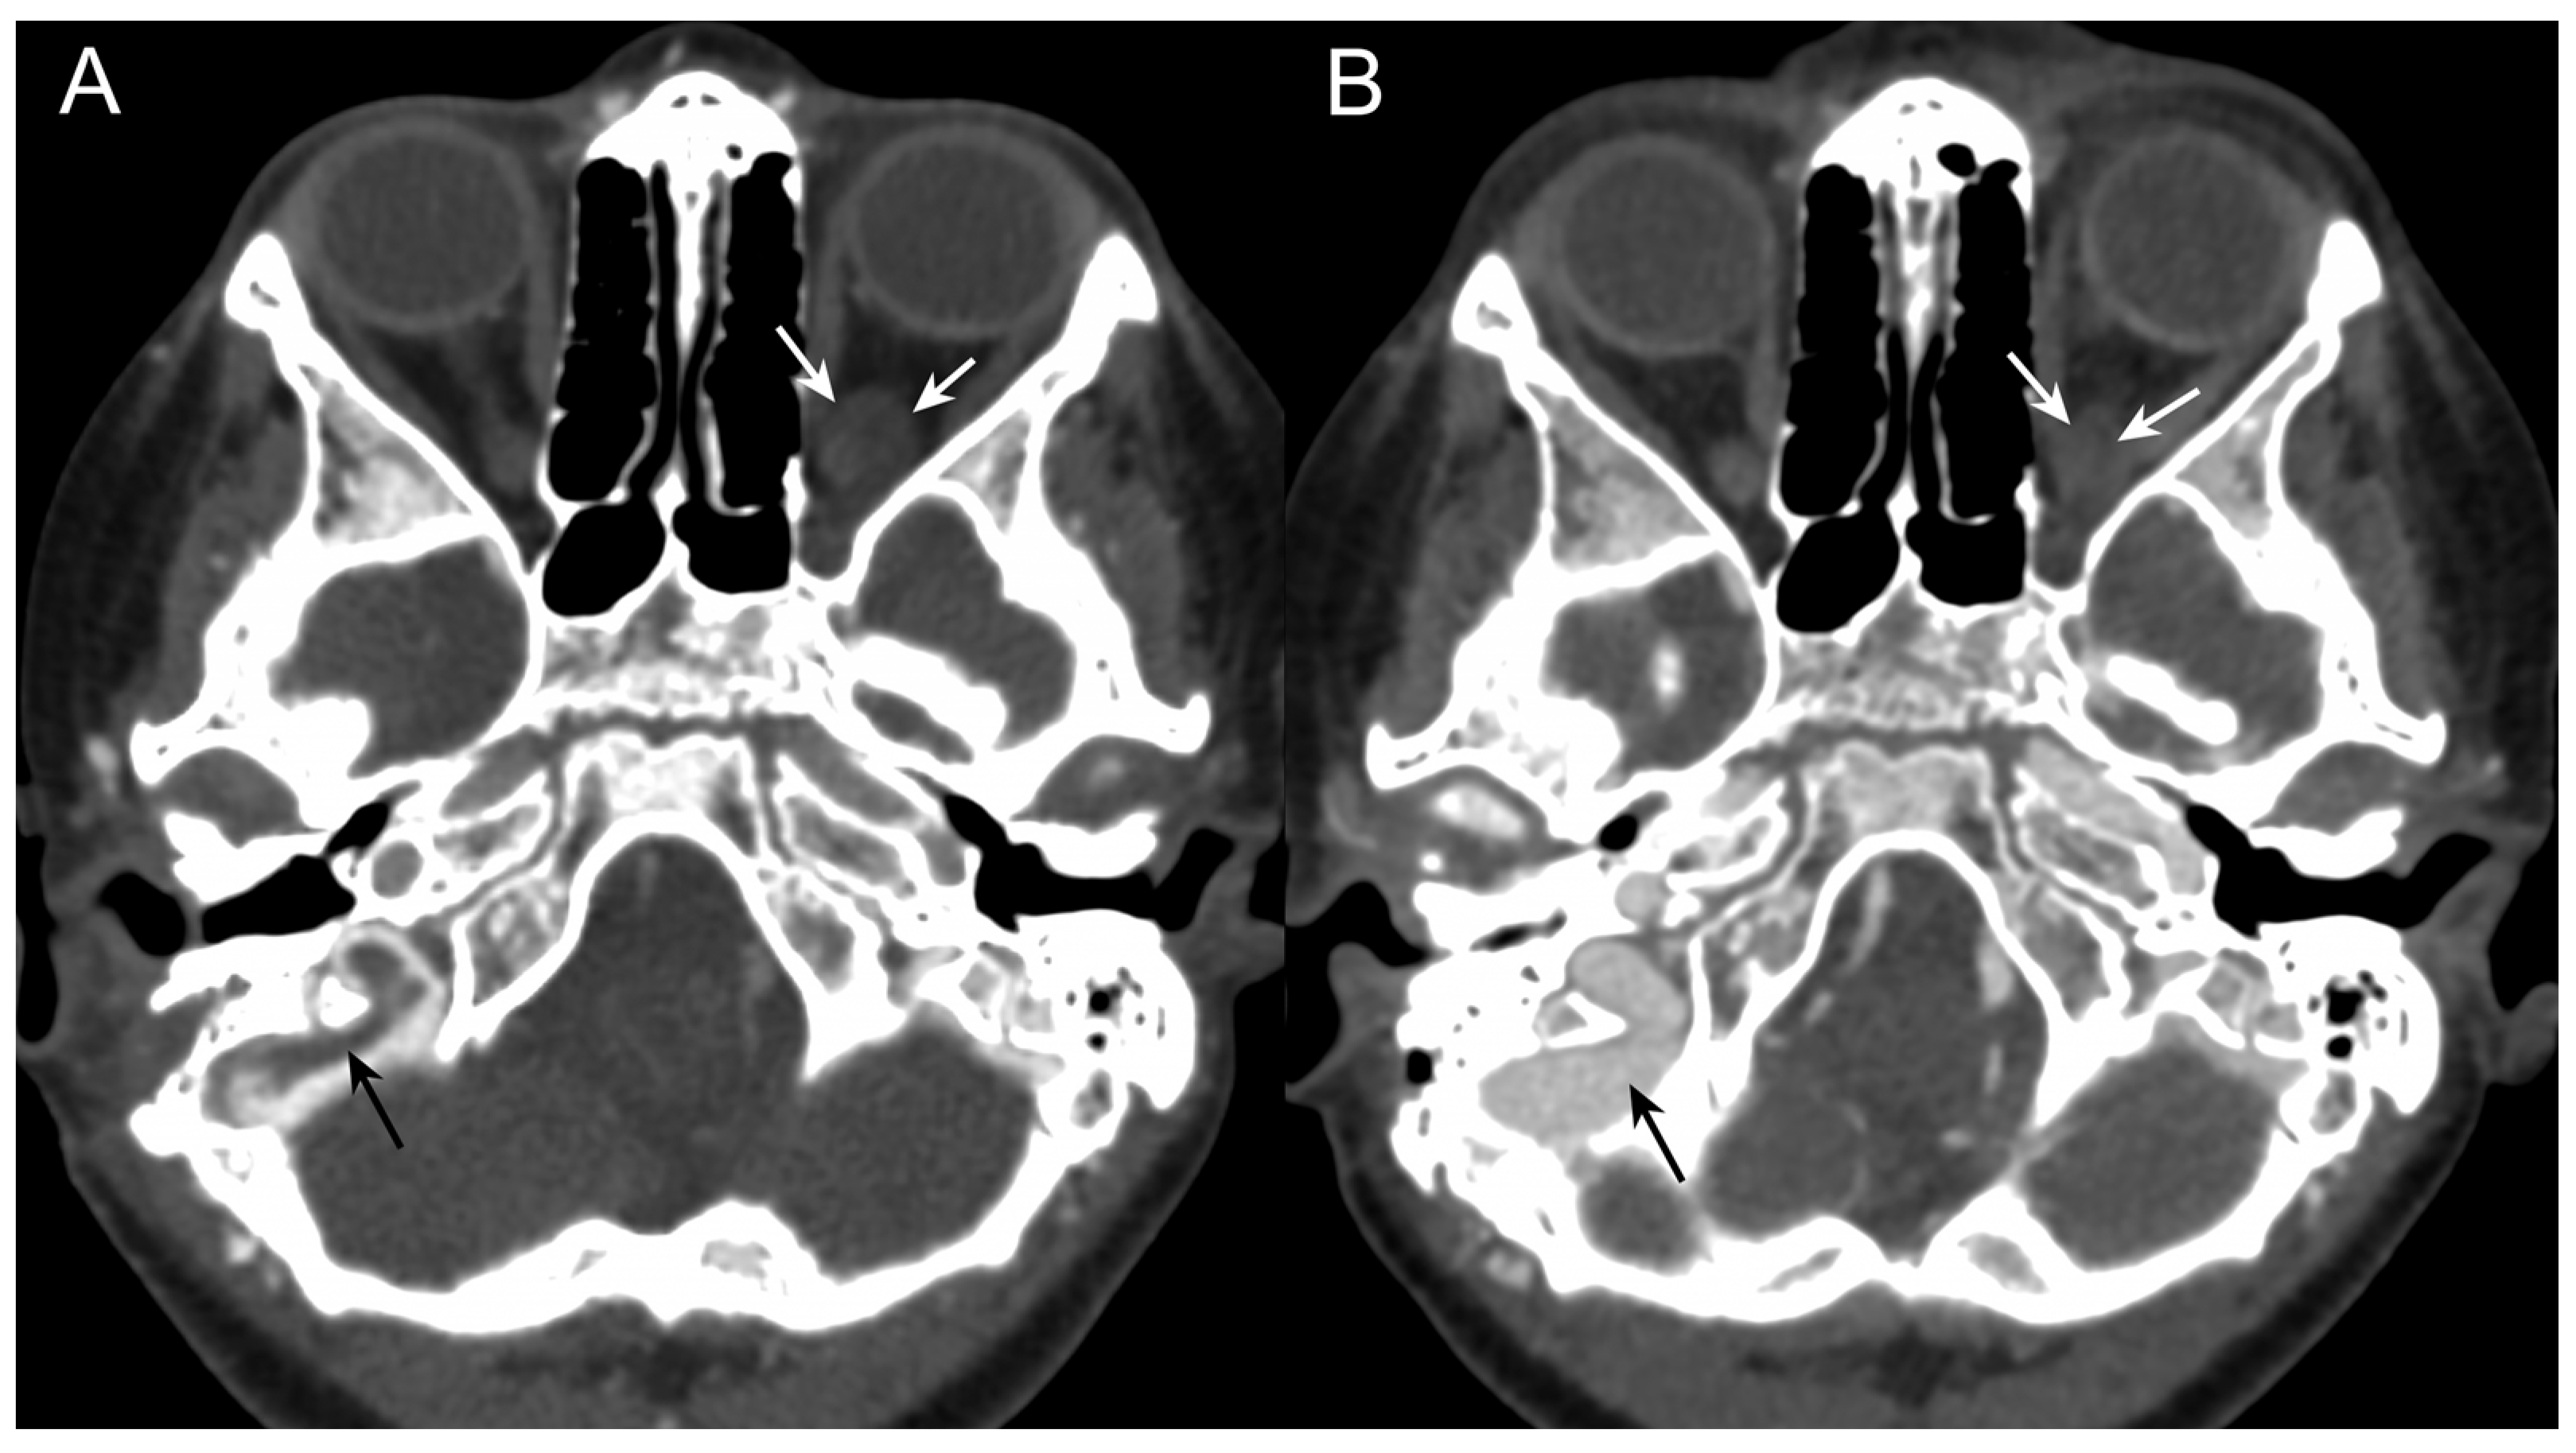

3.1. Case Report